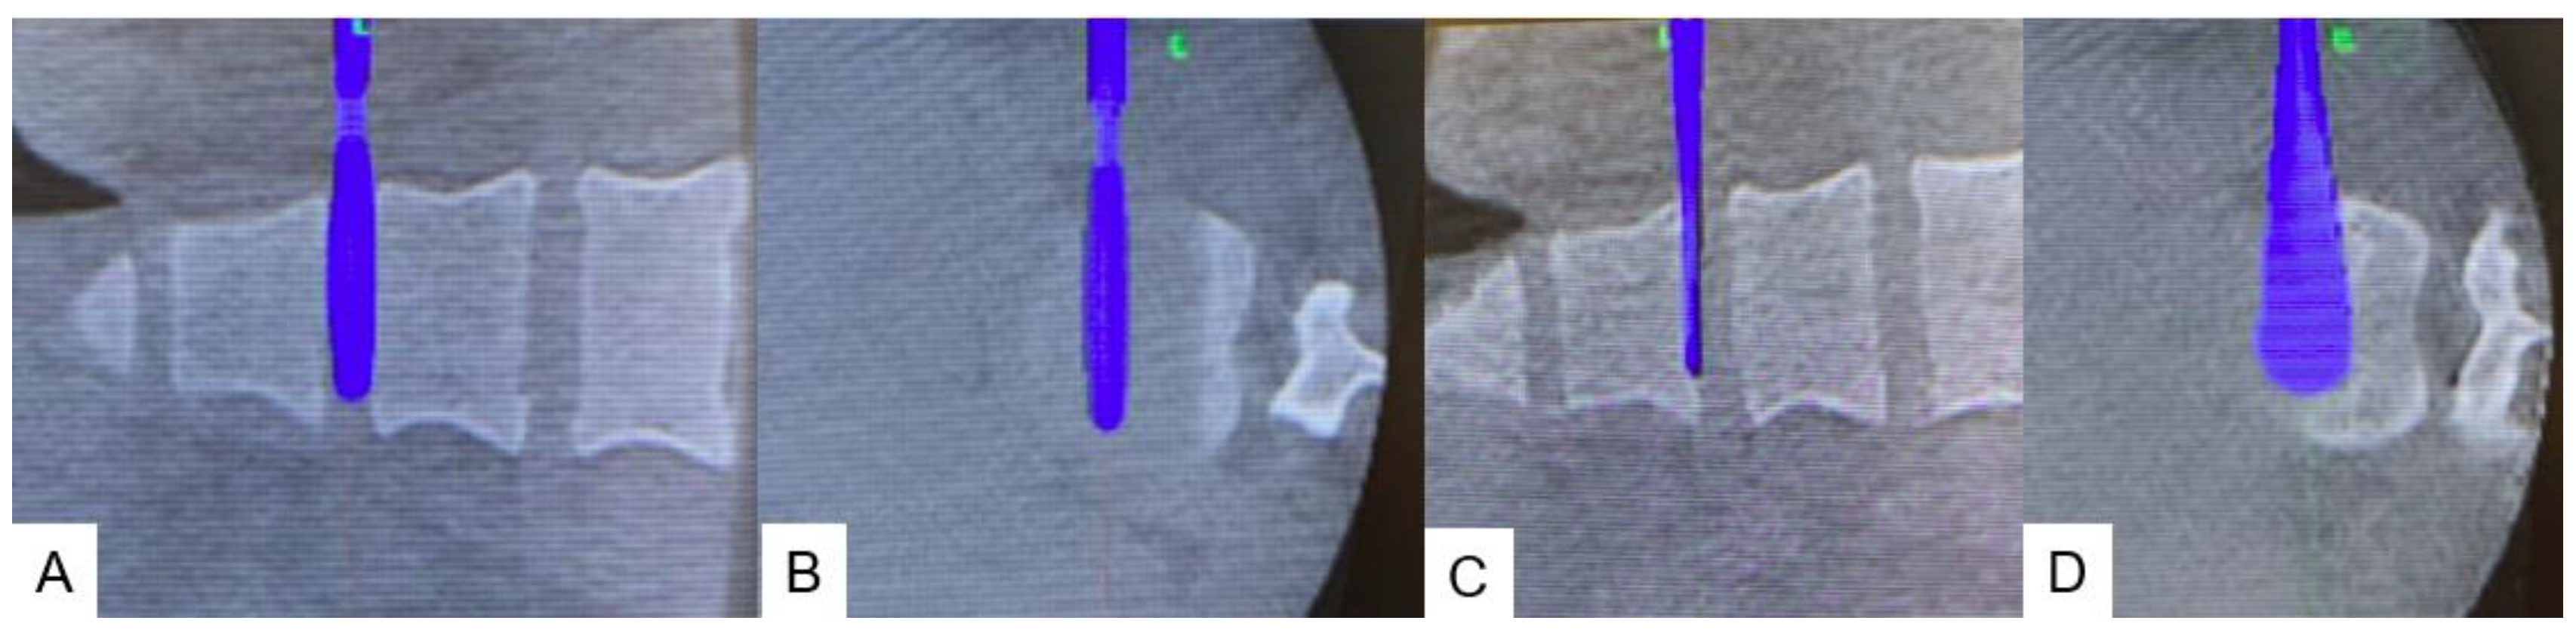

2.4. Surgery

2.4.1. Anterior disectomy

2.4.2. Posterior osteotomy